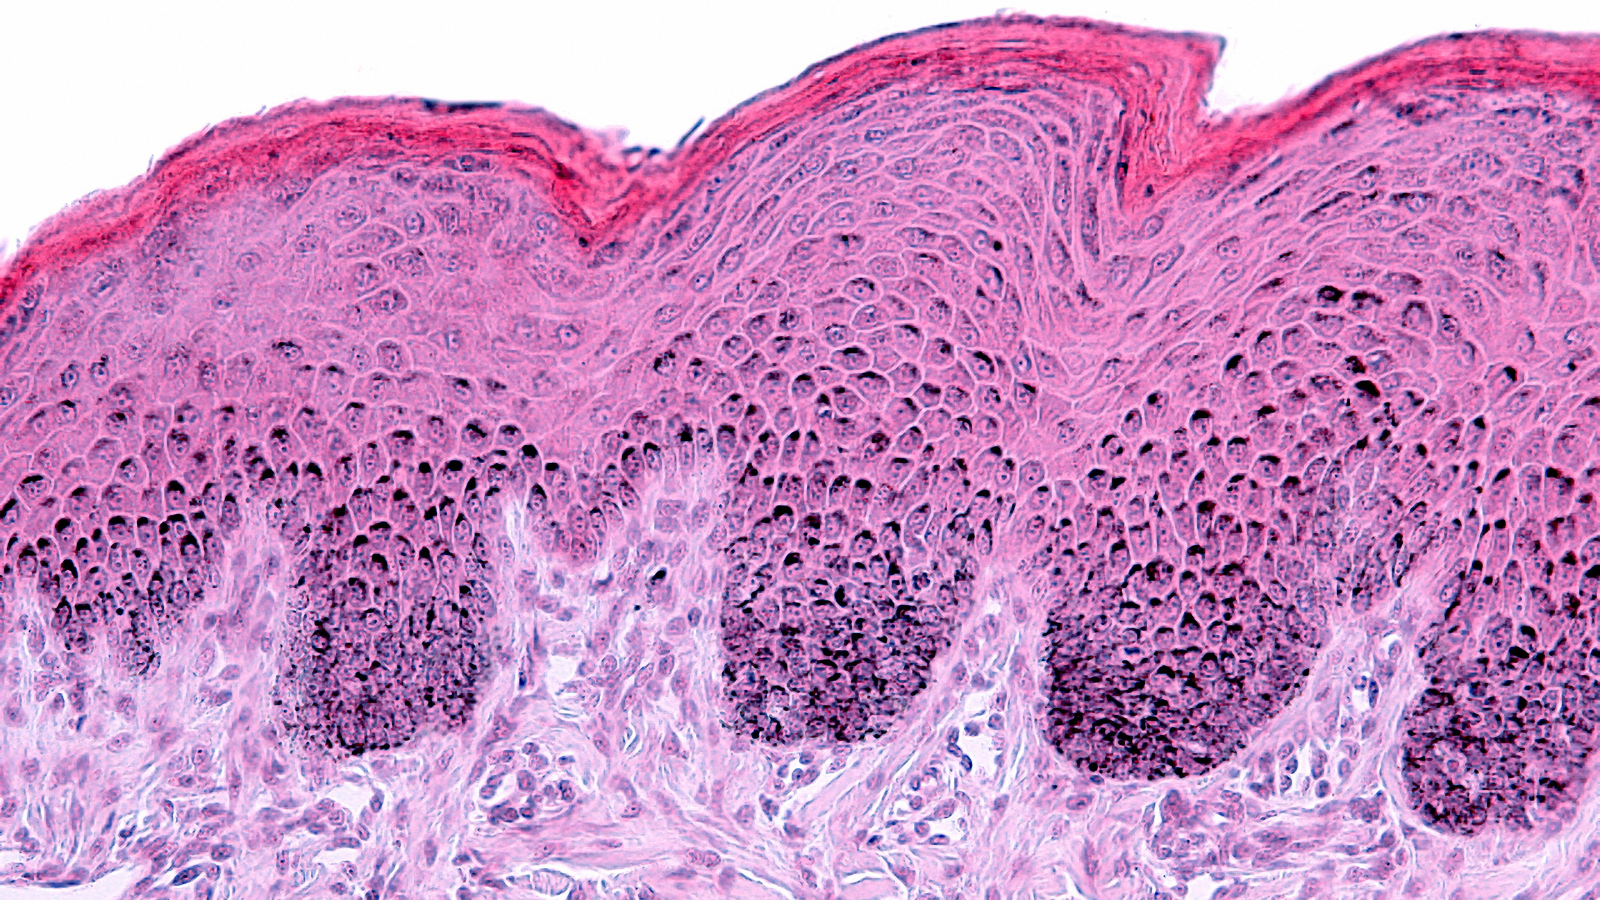

Skin Longevity From Ancient Wisdom to Modern Clinical Evaluation

Explore how non-invasive clinical tools and biomarkers advance skin longevity assessment and substantiate product efficacy.